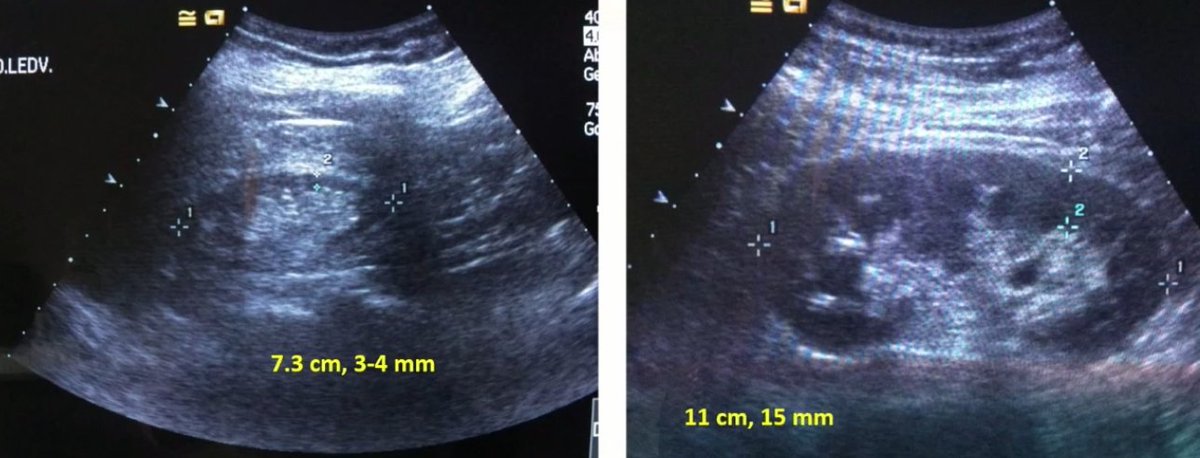

Diferencia entre riñon normal y un riñon atrófico 🧐 #interventionalNephrology #INFellow #POCuSFirst

AvelRomanNeph's tweet image. Diferencia entre riñon normal y un riñon atrófico

🧐

#interventionalNephrology #INFellow #POCuSFirst